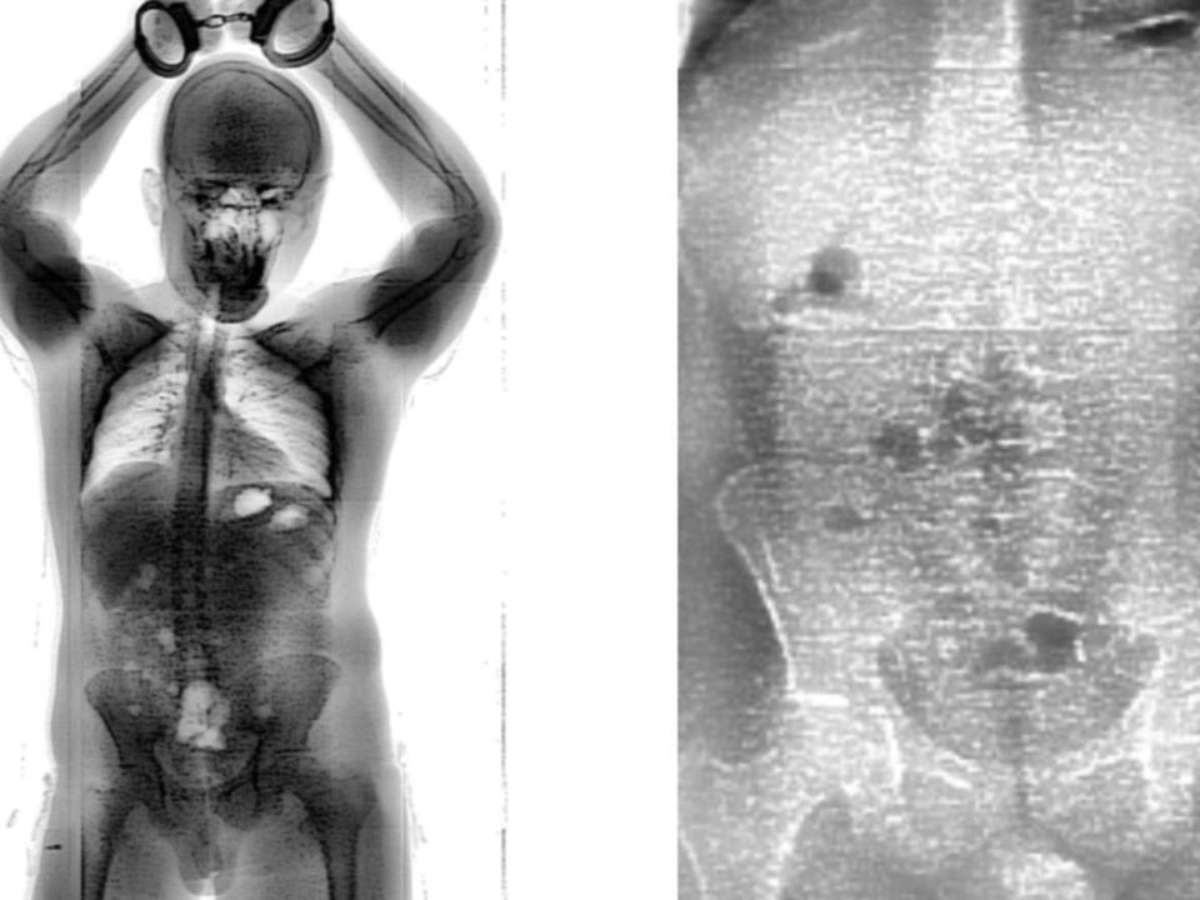

Preso foi flagrado pelo BodyScan com 18 “bolinhas” de maconha no intestino

Raio-x mostrou pacotes de maconha no intestino do homem

Foto: Divulgação/Seap

Segundo a Secretaria de Administração Penitenciária e Ressocialização (Seap), a tentativa de entrar com a droga no local foi frustrada por causa da BodyScan, scanner corporal que apontou alterações na região intestinal do homem. O caso aconteceu na sexta-feira, 15, mas foi revelado pela Seap na noite deste domingo, 17.